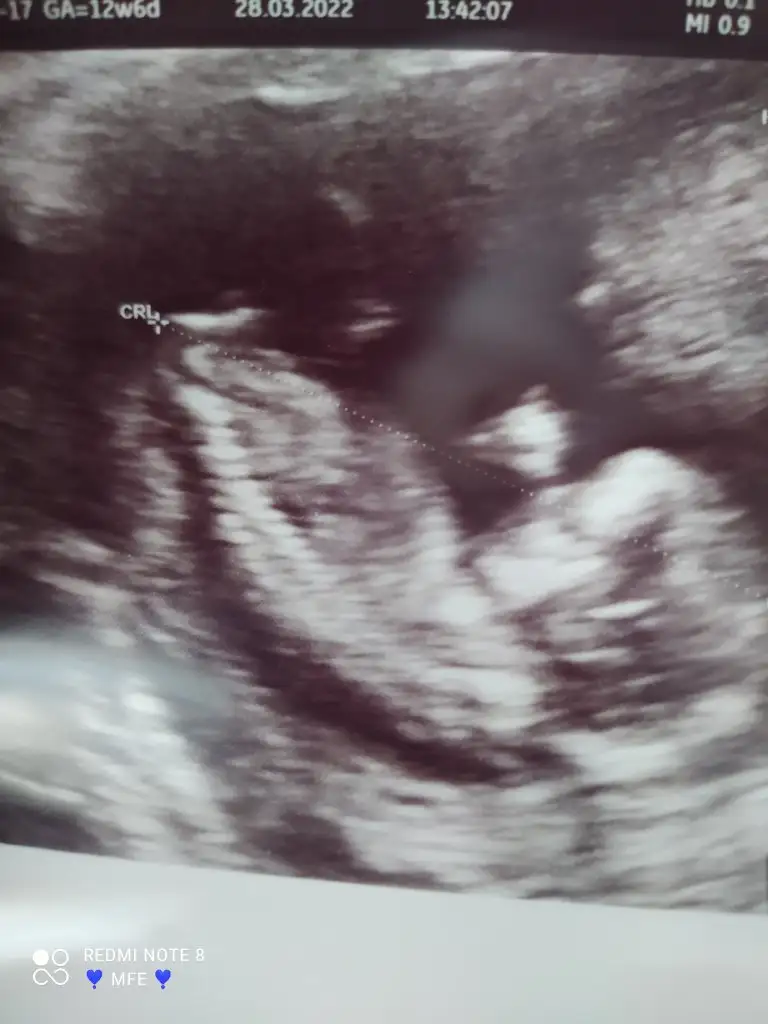

Arkadaşlar yüz üstü yatiyo. Doktor orta resimdeki pipi resmi olarak verdi ama çok da net demedi 1 ay sonra kesin derim dedi. Erkek gibi dedi. Ultrasonu da yeni gelmiş aslında. Içimde öyle bi rahatsızlık var bi tarafim sevinuyo bi tarafim acaba kordon olabilir mi diyo. Sizce nedir erkek diyebilir miyiz

Insalalh canım bende çok sevindim ama doktor kesin deneyimce yinede içinde bisey kaldı söyleyemiyorum kimseye. Ya erkek değilse diye.

Ama baya büyümüş seninki yanılmaz diye düşünüyorum şimdilik söyleme iyice emin olunca artık söylersin

Doktorda aslında sanki emindi ama yine de 1 ay sonra dedi. Diyorum emin olmasa pipi resmi vermezdi. Ama yine de 1 ay sonra kesin derim dedi. E bende merak ediyorum heycanlaniyorum falan bakalım artık. Nisanın 20 sinde belli olur

Sizce nedir nub dan anlayan varmı